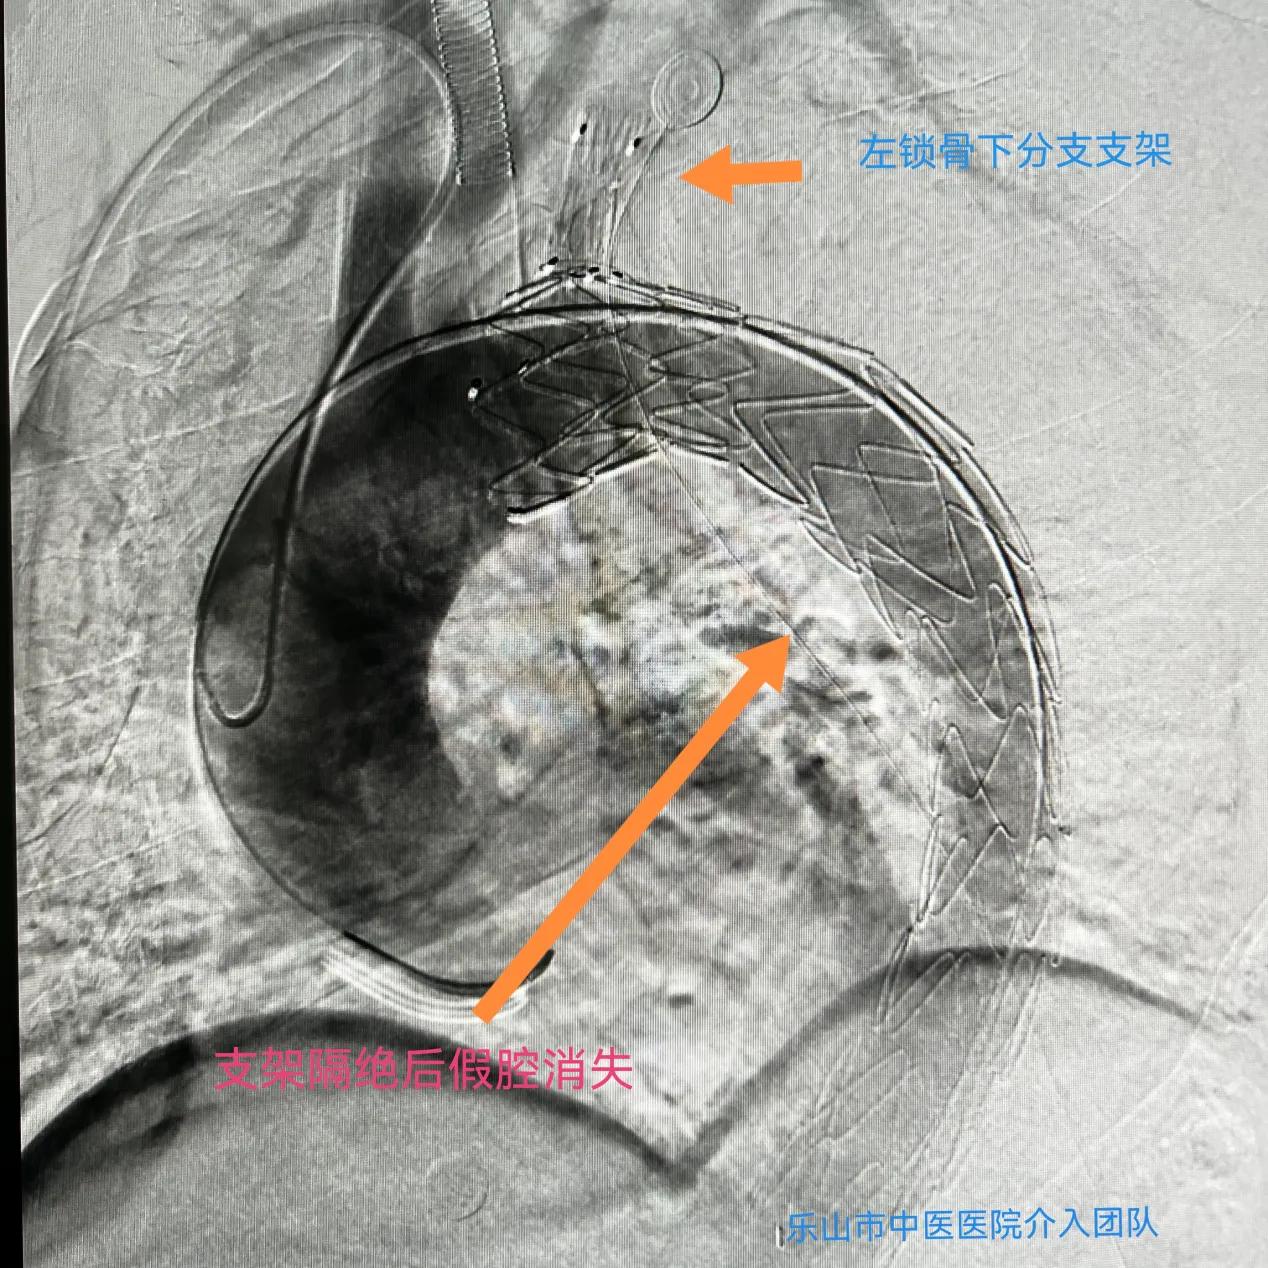

入院后查体,头颅磁共振检查发现右椎动脉夹层动脉瘤;同时,胸腹部增强CT及血管成像提示主动脉夹层(Stanford B型),腹腔干、左肾动脉由假腔供血,肠系膜上动脉由真假腔供血。

考虑到病人病情复杂,介入科团队决定分次进行手术,“先处理椎动脉夹层动脉瘤,待术后平稳后再行二期手术处理主动脉夹层动脉瘤”。10月15日,经周密术前准备,科室副主任刘先军带领医生团队,为患者成功行椎动脉血流导向装置pipeline置入,五天后再行分支型主动脉腹膜支架置入。术中各项指标稳定,目前患者已逐步康复。

“手术采用了目前最先进血流导向装置、分支型主动脉腹膜支架置入技术,这样的技术在同级医院内属领先”,刘先军副主任告诉记者,“而由同一手术团队完成头、胸两个部位血管的手术,这样的‘一站式服务’也避免了病人辗转奔波,缩短了病程,有助于患者的快速康复”。